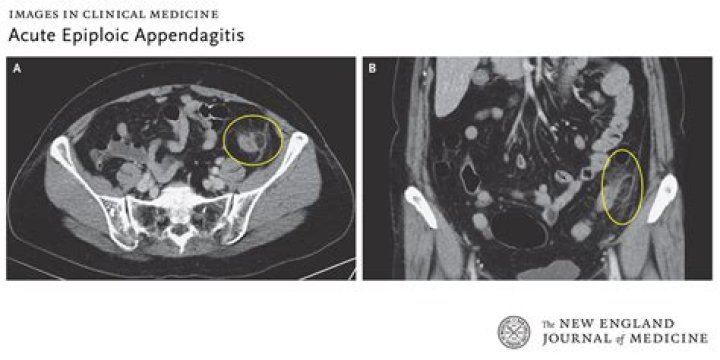

Acute epiploic appendagitis is an uncommon cause of abdominal pain. It is caused by torsion of an epiploic appendage or spontaneous venous thrombosis of a draining appendageal vein. The diagnosis of this condition primarily relies on cross‐sectional imaging and is made most often after computed tomography (CT).

Epiploic appendages are normal outpouchings of peritoneal fat on the anti-mesenteric surface of the colon. Epiploic appendagitis is a benign and self-limited condition [1,2]. Inaccurate diagnosis can lead to unnecessary hospitalizations, antibiotic therapy, and surgical intervention [3-6].